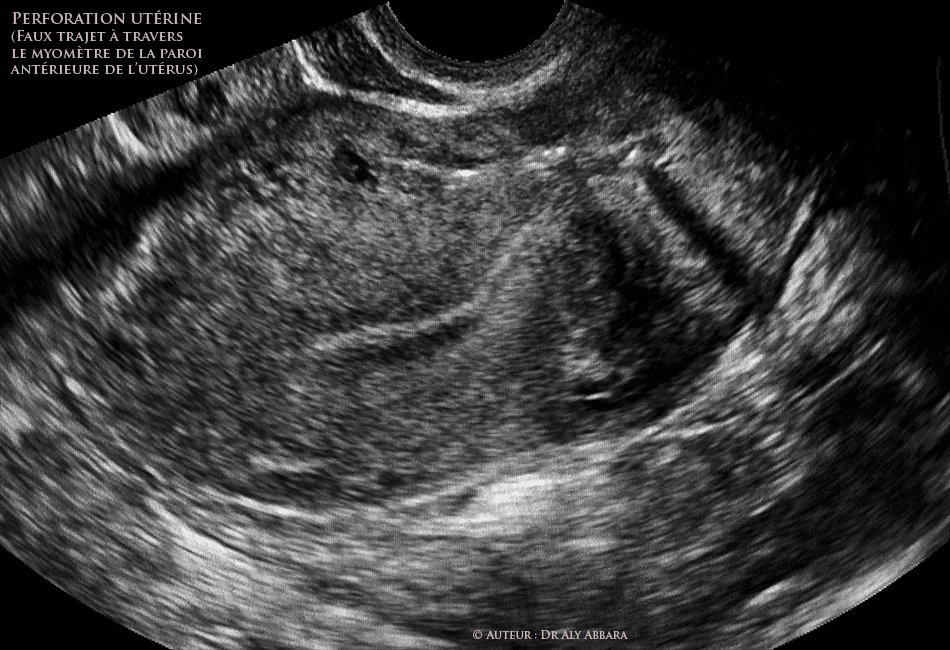

Perforation utérine lors d'une IVG chirurgicale sur utérus malformé, bichorne et bicicatriciel (antcédent de 2 césariennes)

• Utérus : perforation utérine (lors d'une interruption chirurgicale de grossesse) survenant sur un utérus malformé, bicorne unicervical et bicicatriciel (antécédent de 2 césariennes).

La grossesse évoluait dans dans la corne droite de l'utérus et la perforation utérine a eu lieu à travers la paroi antérieure de sa corne gauche ; l'opérateur décrivait une importante difficulté à reconnaître chirurgicalement la corne droite de celle de la gauche.

• Le faux trajet se situe dans le myomètre antérieur, à partir de l'isthme de l'utérus jusqu'à son fond (l'extrémité distale de la bougie de Hegar a traversé le fond pour se trouvée libre dans la cavité péritonéale).

• Il s'agit d'un diagnostic per-opératoire : le faux trajet à travers le myomètre antérieur est identifiable à l'échographique grâce à son aspect linéaire hyper-échogène ; cette typer-échogènécité était visible lors de l'échographie réalisée au cours de l'acte opératoire, mais elle n'était plus observable lors du contrôle échographique effectué deux heures plus tard.